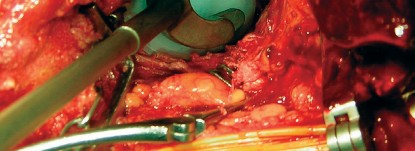

طول عمر مكون الحُق الأسمنتي في مفصل الورك الصناعي يعتمد على التغطية الكافية من عظم المريض والتثبيت الدقيق. جراحة استبدال الورك تتضمن تقييمًا دقيقًا للعظم، إزالة النتوءات العظمية، وتثبيت المكون الأسمنتي لضمان الاستقرار والديمومة طويلة الأمد، مع متابعة دورية لنتائج ممتازة.

الخلاصة الطبية الشاملة: يُعتبر طول عمر مكون الحُق الأسمنتي في مفصل الورك الصناعي حجر الزاوية لنجاح جراحة استبدال مفصل الورك الكلي. يعتمد هذا النجاح بشكل كبير على التخطيط الدقيق قبل الجراحة، والتغطية الكافية من عظم المريض السليم، والتثبيت الأمثل للمكون بتقنيات أسمنتية حديثة. تتضمن الجراحة تقييمًا معمقًا لجودة العظم، إزالة دقيقة للنتوءات العظمية، وتطبيق مادة الأسمنت الطبي الحيوي لضمان تثبيت قوي ومستقر للحُق، مما يكفل الاستقرار والديمومة طويلة الأمد للمفصل الصناعي. مع المتابعة الدورية والالتزام بالبرنامج التأهيلي، يمكن للمرضى التمتع بنتائج ممتازة ونوعية حياة محسنة لسنوات عديدة. في صنعاء، يبرز الأستاذ الدكتور محمد هطيف كخبير رائد في هذا المجال، حيث يجمع بين الخبرة العميقة والتقنيات المتطورة لتقديم أفضل رعاية جراحية.